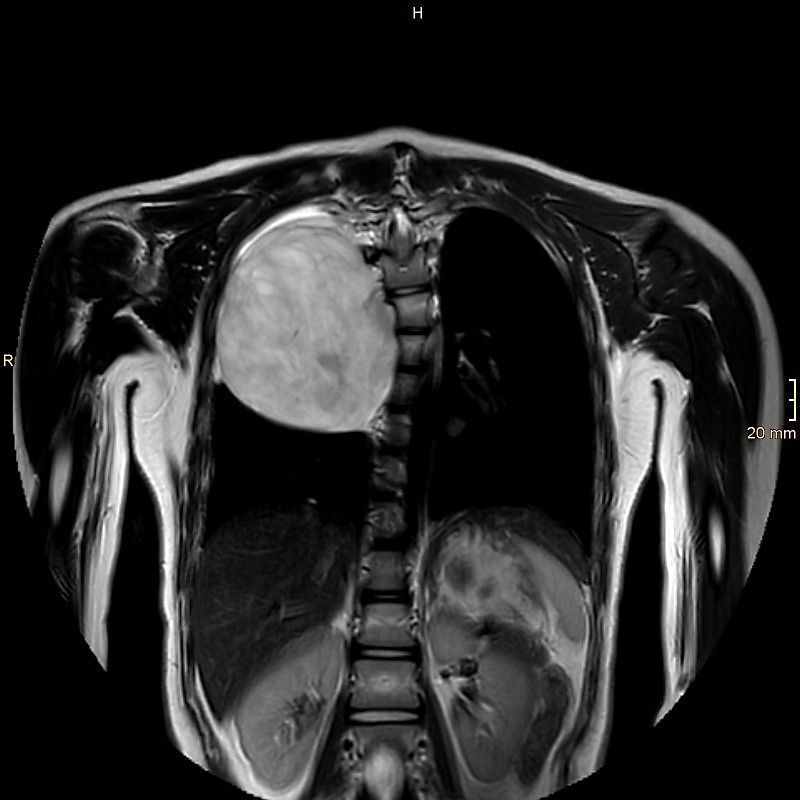

Nach der Flucht aus der Heimat wurde bei Sadaf bei einer Routineuntersuchung in Kärnten ein zehn Zentimeter großer Tumor festgestellt, der an der Wirbelsäule saß und bereits die Lunge verdrängte. Die Schülerin kam sofort zur weiteren Abklärung ins Eltern-Kind-Zentrum am Klinikum Klagenfurt. "Wir haben das Mädchen genau untersucht und konnten glücklicherweise feststellen, dass der Tumor lokal beschränkt und ohne Hinweis auf Bösartigkeit war", erzählt Jörg Jahnel, Abteilungsvorstand der Kinder- und Jugendheilkunde laut "Kleiner Zeitung".

Der Tumor wuchs von der Wirbelsäule aus in den Brustraum.

Kabeg